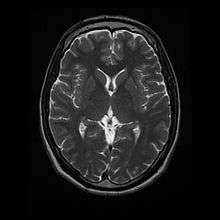

- T2: CSF is light, but fat (and thus white matter) is darker than with T1. T2 is useful for visualizing pathology.[14]

Normal axial T2-weighted MR image of the brain.